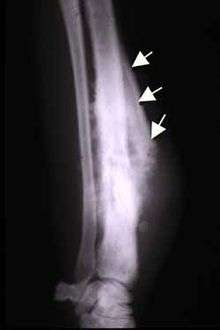

Codman triangle (previously referred to as Codman's triangle) is the triangular area of new subperiosteal bone that is created when a lesion, often a tumour, raises the periosteum away from the bone.[1] A Codman triangle is not actually a full triangle. Instead it is often a pseudotriangle on radiographic findings with ossification on the original bone and one additional side of the triangle which forms a two sided triangle with one open side. This two sided appearance is generated due to a tumor (or growth) that is growing at a rate which is faster than the periosteum can grow or expand, so instead of dimpling, the periosteum tears away and provides ossification on the second edge of the triangle.[2]

The main causes for this sign are osteosarcoma, Ewing's sarcoma, eumycetoma, and a subperiosteal abscess.[3][4]